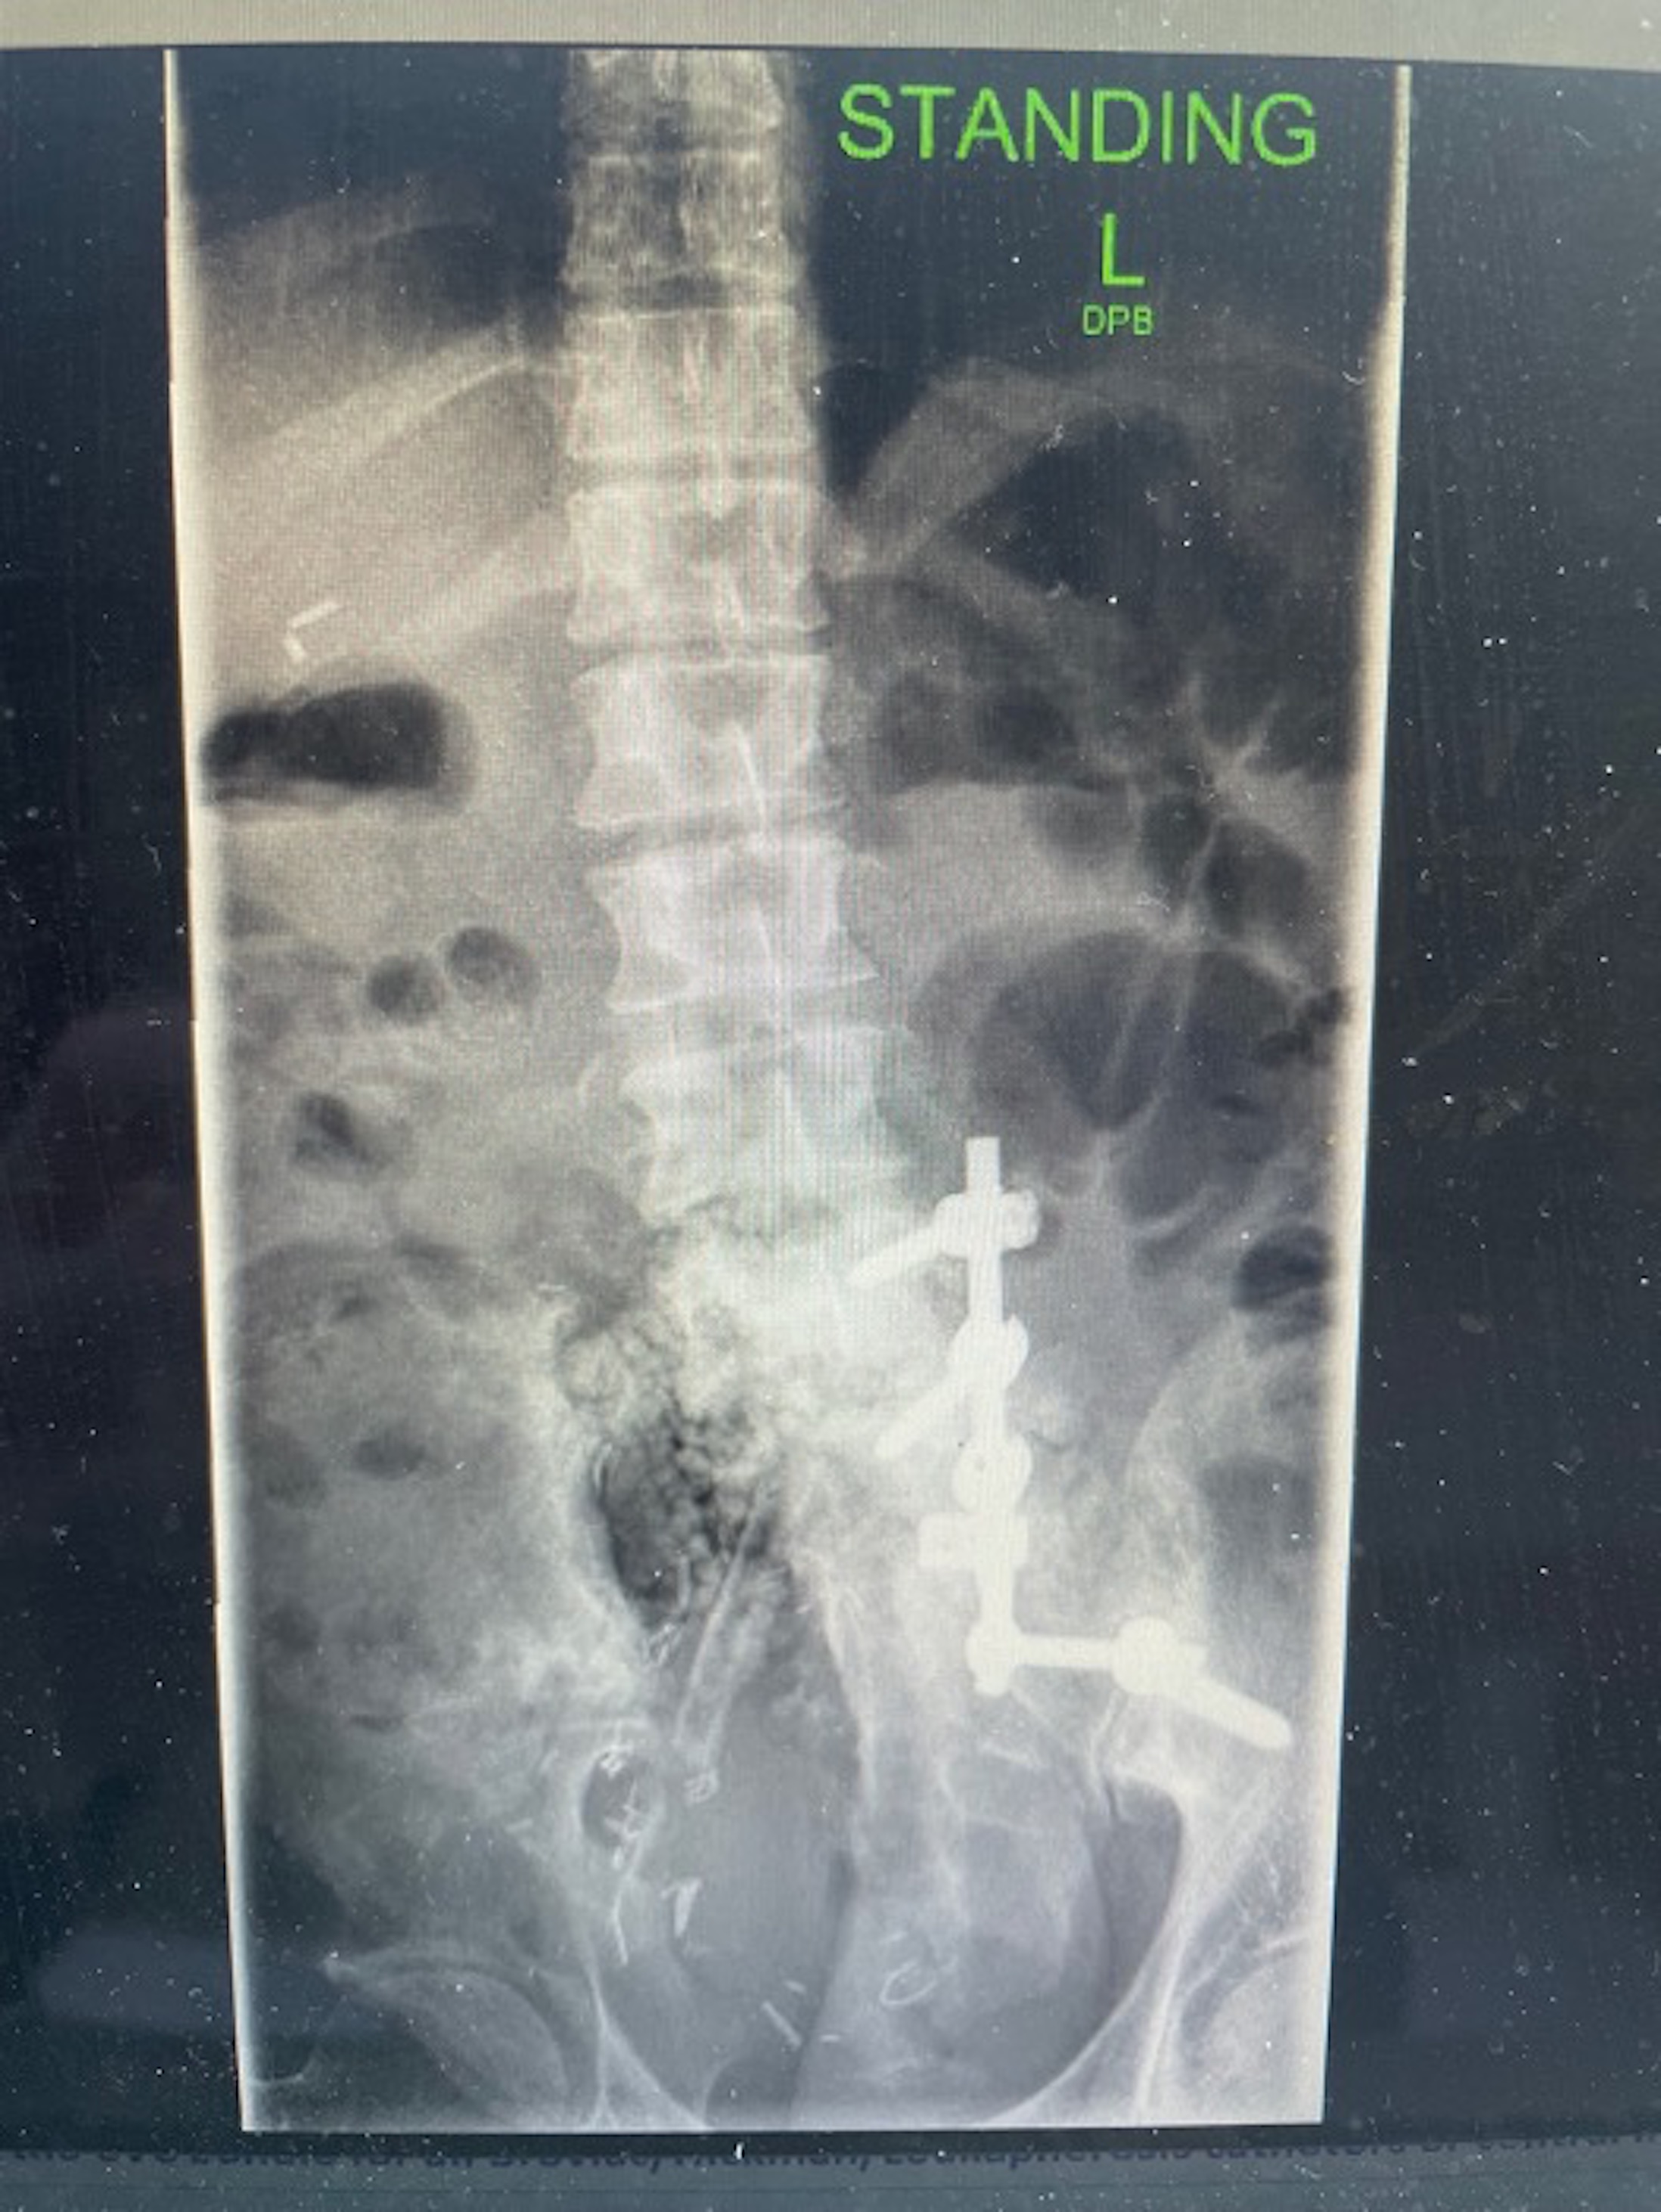

A 33-year-old man was referred to the plastic surgery service for management of a complex lower back wound. His medical history is significant for right sacral Ewing’s sarcoma diagnosed at the age of 17 years. The tumor was initially treated with chemoradiation but recurred locally 2 years later, requiring an extended right hemisacrectomy. Spinopelvic stabilization was performed with pedicle screws and rods and allograft fibula. Right L5 and all sacral nerve roots were resected, resulting in partial right lower limb paralysis, leaving him crutch dependent for ambulation.

He now presents 11 years later with an infection of the L4-L5 fixation site, leading to formation of a sinus tract. He was taken to the operating room by the orthopedic surgery service who performed debridement of nonviable tissue, removal of spinal instrumentation, and placement of antibiotic beads. The wound is now open and radiated (Figures 1 and 2).